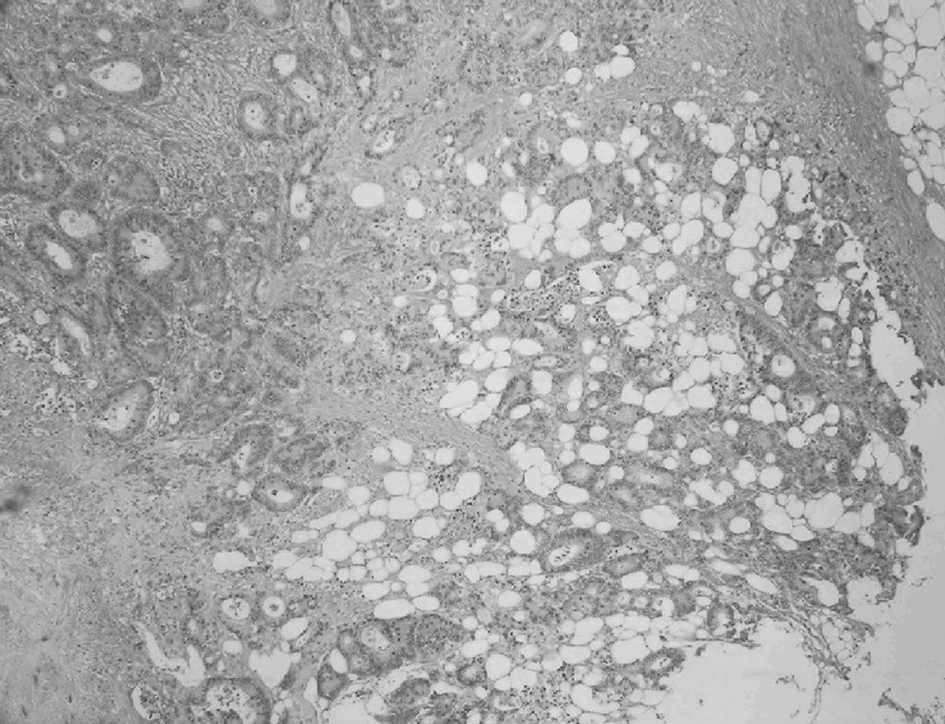

Fig. 3. Patrón de invasión infiltrante: glándulas neoplásicas infiltrando el tejido adiposo pericólico (hematoxilina-eosina, x4).

Las características del patrón de invasión tumoral en los pacientes seleccionados se estudiaron en muestras de tumor conservadas en el archivo de tejidos del Servicio de Anatomía Patológica del Hospital Universitario Médico-Quirúrgico de Jaén. Se han descrito 2 modelos de crecimiento de los márgenes del tumor: infiltrante y no infiltrante o desplazante (fig. 1). En este estudio se han considerado como criterios diagnósticos de configuración infiltrante del patrón de invasión tumoral los descritos por Jass et al2 y que posteriormente fueron adoptados por el American Joint Committee (AJC)3: la disección del tumor a través del espesor de la muscular propia (fig. 2), la disección del tejido adiposo mesentérico por grupos o cordones irregulares de células (fig. 3) y la invasión perineural (fig. 4). La presencia de cualquiera de estos 3 patrones en un tumor es suficiente para considerarlo como "patrón de invasión tumoral infiltrante". En nuestro estudio se examinaron las secciones histológicas teñidas con hematoxilina-eosina para identificar, en cada caso, la presencia de uno o varios de los criterios para considerar el patrón de invasión como infiltrante o, en ausencia de ellos, como desplazante.